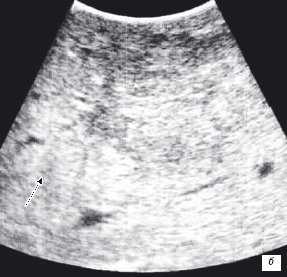

Клинический пример N2. Пациентка Р. находилась на лечении в ГУРОНЦ РАМН. При прохождении обследования был установлен диагноз рак толстой кишки. По данным ультразвуковой компьютерной томографии на фоне выраженной диффузной неоднородности паренхимы печени очаговые образования не определялись. При проведении ангиографии и компьютерной томографии так же убедительных данных за наличие метастазов в печень получено не было. При интраоперационном ультразвуковом исследовании были выявлены два очага, характерными особенностями которых являлись малые размеры (0,2 - 0,4 см), а так же нечеткость контуров и изоэхогенность структуры (рис. 1 а,б).

Рис. 1. Метастатические очаги (стрелки) в печени при интраоперационной ультразвуковой томографии.